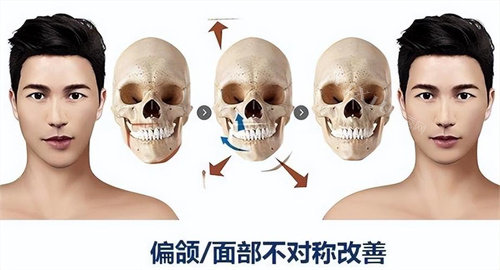

何锦泉医生是广州广大口腔医院的颌面整形医师,拥有丰富的正颌手术经验。他专注于骨性地包天、凸嘴、偏颌等复杂颌面畸形的矫正,尤其擅长运用3D导板技术进行精细手术。3D导板技术通过术前CT扫描建模,模拟截骨范围和骨骼移动轨迹,误差可控制在0.1毫米以内。这种技术不仅提高了手术的精细度,还降低了术后并发症的风险。

何锦泉医生为张先生进行了详细的面部检查和三维模型分析,发现其凸嘴主要是由于上颌骨前突所致。于是,何医生制定了上颌骨后移的手术方案,并结合3D导板技术进行精细定位。

广州广大口腔医院凭借其新型的3D导板技术和何锦泉医生的正规技能,在正颌手术领域取得了显著的成效。无论是骨性凸嘴、地包天还是面部不对称,广大口腔都能为患者提供个性化的解决方案,帮助他们重获自信的笑容。